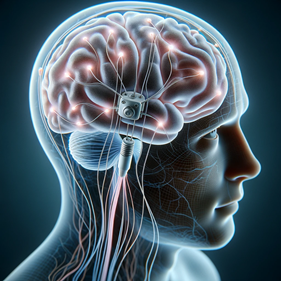

- Deep brain stimulation (DBS)

Deep Brain Stimulation (DBS) was first used to treat movement disorders such as Parkinson’s disease. In this technique, electrodes are implanted in specific areas of the brain and connected to a pulse generator that is surgically placed under the skin in the upper chest. The brain can be precisely stimulated with great spatial resolution.

The chest implant requires a battery replacement every 3 to 5 years and is programmed by using a special remote control from outside the body. As it is obvious, this technique requires surgery and so is very invasive.